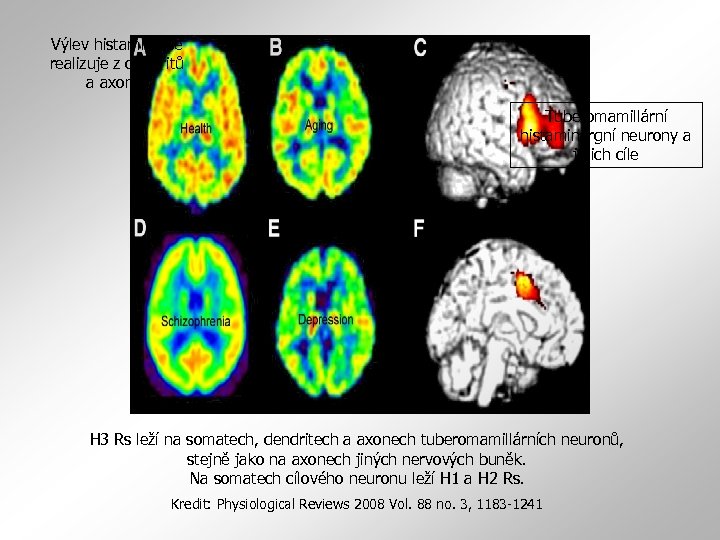

Výlev histaminu se realizuje z dendritů a axonů. Tuberomamillární histaminergní neurony a jejich cíle H 3 Rs leží na somatech, dendritech a axonech tuberomamillárních neuronů, stejně jako na axonech jiných nervových buněk. Na somatech cílového neuronu leží H 1 a H 2 Rs. Kredit: Physiological Reviews 2008 Vol. 88 no. 3, 1183 -1241

Změny ve vazbě na H 1 Rs v lidském mozku A, C –zdravý mozek: silný H 1 Rs signál i aktivita v anteriorní cingulátní kůře B, D - změny ve vazbě na H 1 Rs při stárnutí a u schizofreniků E, F - deprese a pokles vazby v prefrontální kůře i v anteriorní cingulátní kůře Kredit: Physiological Reviews 2008 Vol. 88 no. 3, 1183 -1241